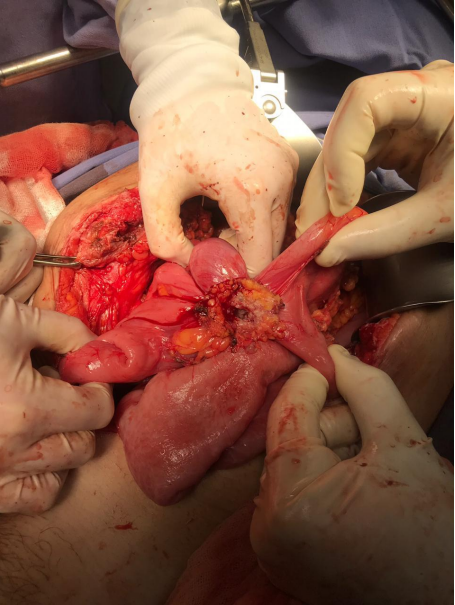

Por los hallazgos, se decidió realizar una laparotomía exploradora. Encontrando una fístula entero-cutánea y entero-entérica formada por un conglomerado de asas intestinales. Se encontraron 5 asas comunicadas entre ellas (Foto 3); el extremo proximal a 80cm del ángulo de Treitz y el extremo distal a 140 cm de la íleo-transverso anastomosis; se reconoce recaída tumoral en la fístula (anatomía patológica extemporánea: Adenocarcinoma). Se resecó el trayecto fistuloso en la pared abdominal y las asas intestinales involucradas (Foto 4).

Foto 3: Conglomerado de 5 asas intestinales con comunicación a fistula entero-cutánea/entero-entérica